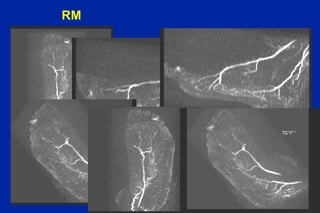

Este documento resume los principales tipos y técnicas de angiografía. Describe brevemente la angiografía, arteriografía, flebografía y linfografía, así como las técnicas de contraste y materiales utilizados. También explica los principales accesos vasculares, la técnica de Seldinger, la angiografía por sustracción digital y algunas técnicas endovasculares comunes.